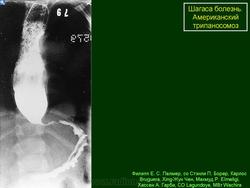

На протяжении второй стадии паразиты концентрируются, в основном, в сердце или мускулатуре пищеварительного тракта. До 30% пациентов страдает от нарушений сердечной деятельности и до 10% – от изменений в органах пищеварения (характерна гипертрофия пищевода или толстой кишки), нервной системе или целом ряде органов. В последующие годы инфекция может приводить к внезапной смерти или сердечной недостаточности, вызываемой прогрессивным разрушением сердечной мышцы.